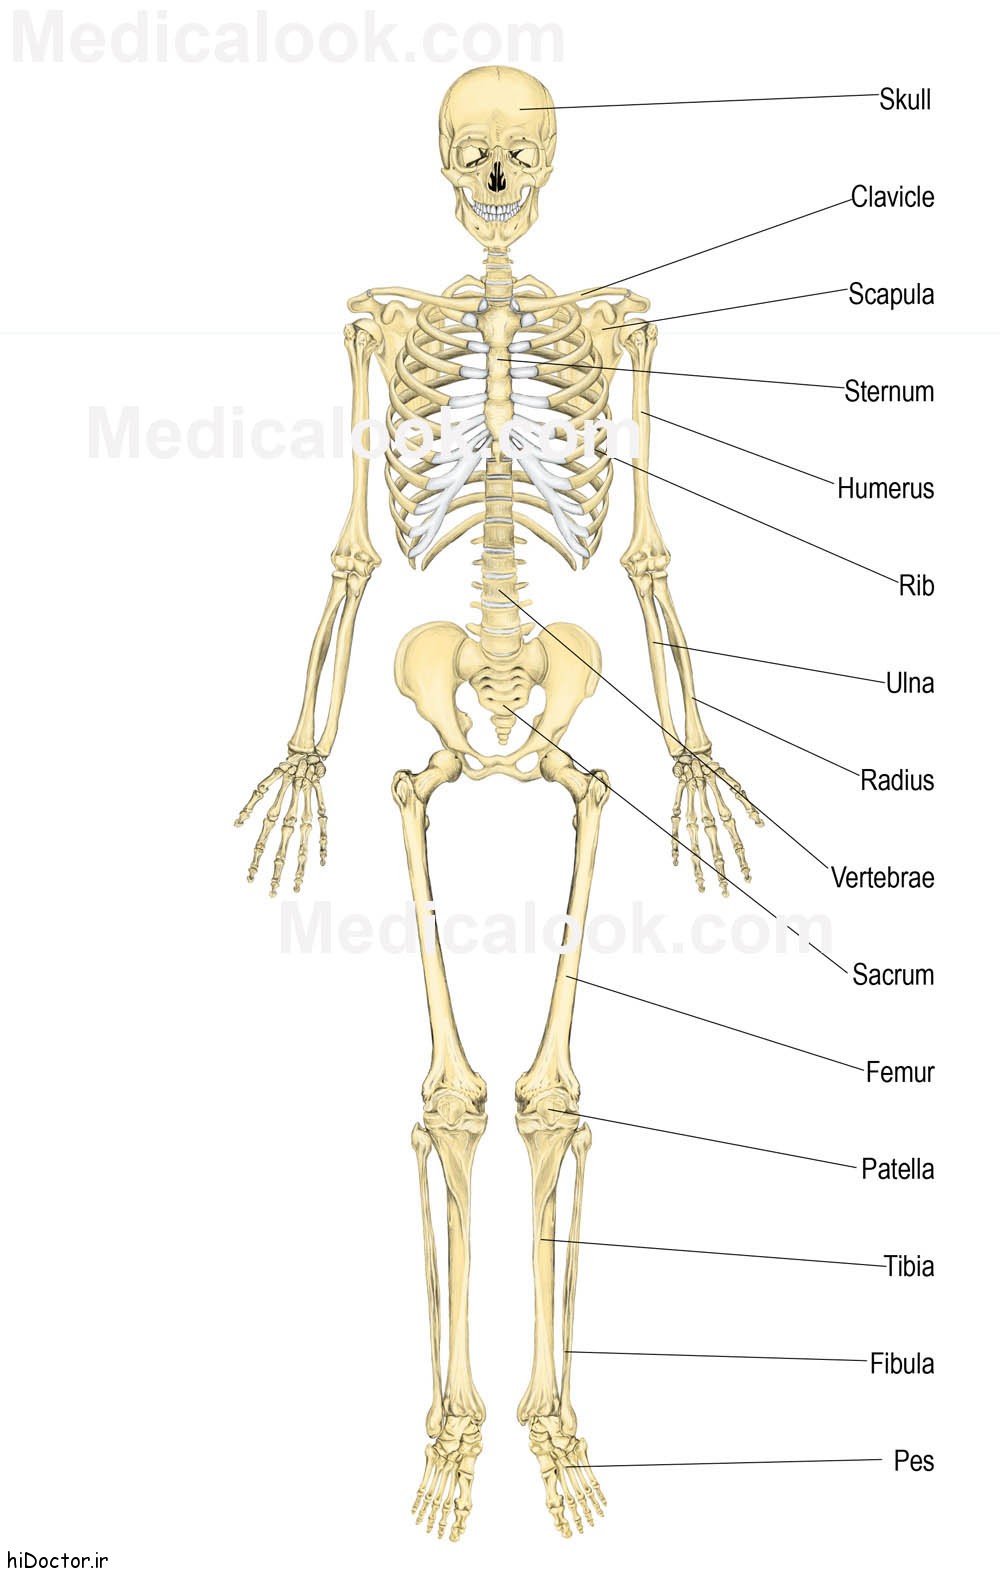

عکس اسکلت بدن انسان

آناتومی سه بعدی بدن انسان عکس گرافی بدن.

عکس اسکلت بدن انسان. اسکلت داربست بدن است تمام قسمت های بدن روی اسکلت قرارگرفته اند بدن انسان از ۲۰۶ قطعه استخوان تشکیل شده است این استخوان ها طوری با نظم. هر قسمت بدن از انواع مختلف سلول تشکیل شده است. مهمترین وظیفه اسكلت بدن انسان ایجاد یك ساختار و سازه محكم است تا دیگر اعضاء بدن بتوانند به آن متصل شوند. سازه و چهارچوب اصلی بدن.

اسکلت داربست بدن است تمام قسمت های بدن روی اسکلت قرارگرفته اند بدن انسان از ۲۰۶ قطعه استخوان تشکیل شده است این استخوان ها طوری با نظم کنار هم قرار گرفته اند که انسان را قادر می سازد حرکات دقیقی داشته باشد. بدون اسكلت بدن مانند كرم شل و نرم است و این نوع شكل بندی نمیتواند. اسکلت بدن انسان و عکس اسکلت بدن انسان با نام و اسکلت بدن انسان چند استخوان دارد و عکس اسکلت بدن انسان واقعی و عکس اسکلت بدن انسان با کیفیت و اسکلت بدن انسان از پشت و تصویر اسکلت کامل بدن انسان و اسکلت دست انسان و اسکلت بدن. معرفی بدن انسان اسکلیت.

اسکلت داربست بدن است تمام قسمت های بدن روی اسکلت قرارگرفته اند بدن انسان از ۲۰۶ قطعه استخوان تشکیل شده است این استخوان ها طوری با نظم کنار هم قرار گرفته اند که انسان را قادر می سازد حرکات دقیقی داشته باشد. استخوان یک نسج بسیار محکم است زیرا در ترکیب آن منرالها مانند کلسیم و دیگر وجود. اسکلت داربست بدن است تمام قسمت های بدن روی اسکلت قرارگرفته اند بدن انسان از ۲۰۶ قطعه استخوان تشکیل شده است این استخوان ها طوری با نظم کنار هم قرار گرفته اند که انسان را قادر می سازد حرکات دقیقی داشته باشد. آناتومی سه بعدی بدن انسان عکس گرافی بدن امعاء و احشاء بدن آناتومی سه بعدی بدن انسان عکس گرافی بدن امعاء و احشاء بدن قلب کبد روده.

اسکلت داربست بدن است تمام قسمت های بدن روی اسکلت قرارگرفته اند بدن انسان از 206 قطعه استخوان تشکیل شده است این استخوان ها طوری با نظم کنار هم قرار گرفته اند که انسان را قادر می سازد حرکات دقیقی داشته باشد. اسكلت به بدن شكل میدهد. عکس اسکلت بدن انسان زن و مرد آناتومی ساتین 16 سپتامبر 2017.